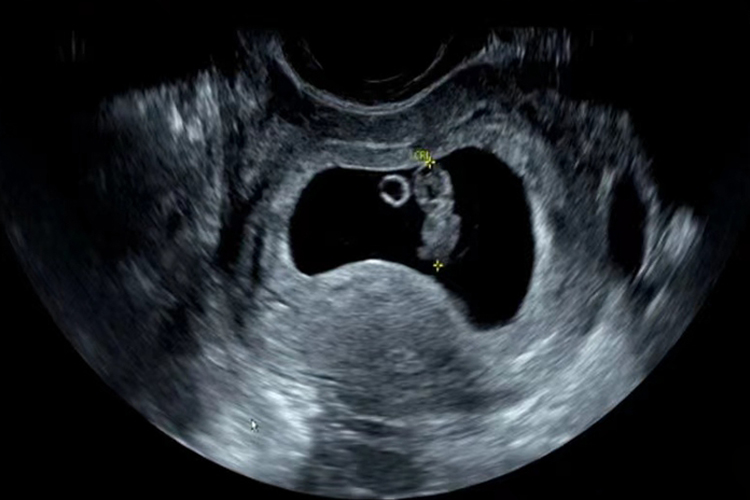

孕8周胎儿约有2厘米长,头部更加直立,出现眼睛,眼睑几乎可以盖住眼睛,但还没有脸和外耳道。胚胎尾部正在消失,手指和脚趾长得更长,胳膊也变长,手在手腕的地方弯曲活动。胎儿的膝关节和肘关节已经形成,也能够弯曲,但外生殖器还没发育完全。